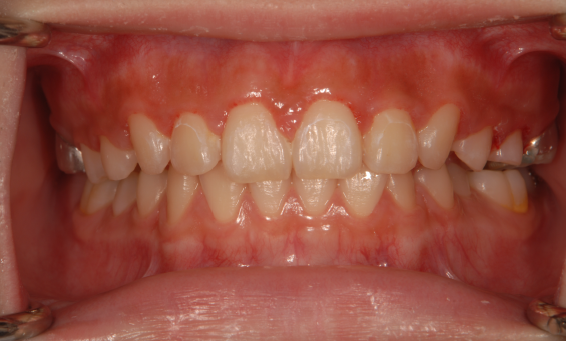

顎顔面矯正は、「急速拡大装置」を利用し、正中口蓋縫合と呼ばれる部分を広げ、顎骨の成長を促していきます。下の画像のように「ねじ」を回すことで装置を徐々に広げていきます。

この装置以外にも、ケースによっては「マイオブレース」と呼ばれる装置や、お口の発育を促す「トレーニング」を併用することもあります。矯正治療で「トレーニング?」と思われるかもしれません。トレーニング(筋機能訓練)の必要性に関して簡単にご説明します。

先ほどもお伝えしましたが、「歯並びを悪くする癖」には口呼吸以外にも、舌癖、逆嚥下の他、頬杖、唇噛み、うつぶせ寝/横向き寝等があります。これらを改善することで、歯並びが悪くなる原因がなくなり、自然と正しい方向に歯は並んでくれます。当院ではこの悪癖を「トレーニング(筋機能訓練)」で改善していきます。